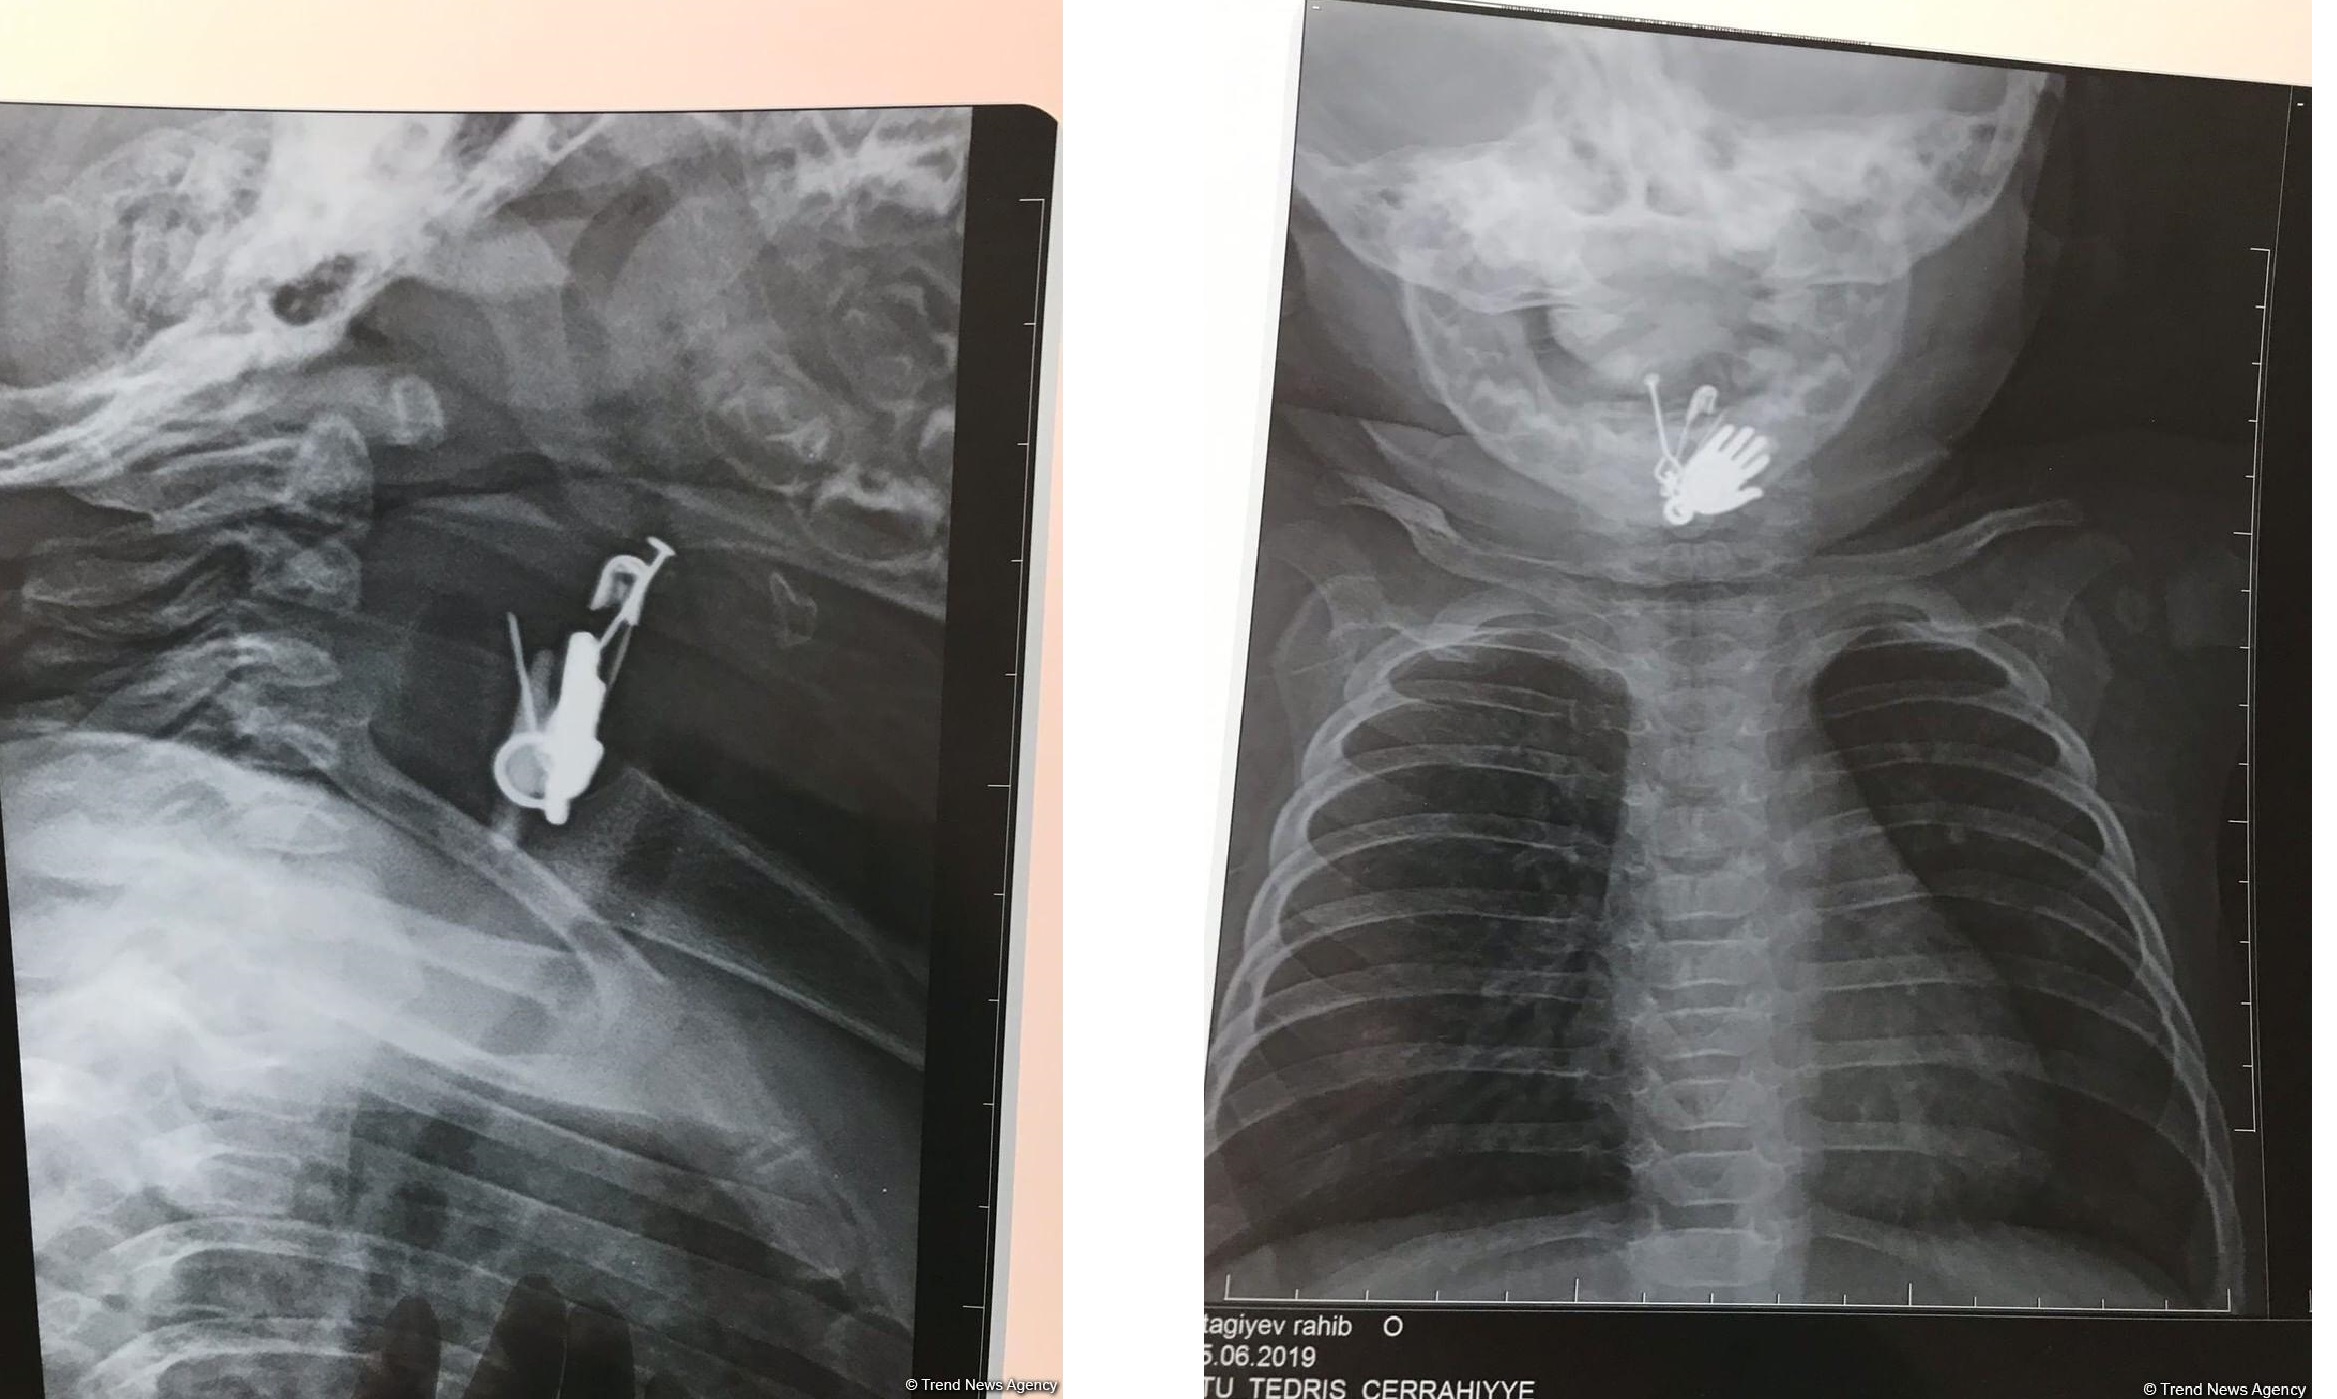

\"\"

Azərbaycanda altı aylıq körpənin mədəsindən sancaq və digər cisimlər çıxarılıb. Oxu24.com -un   məlumatına görə, hadisə Biləsuvar rayonunda baş verib. Belə ki, sözügedən rayonda valideyn yeni doğulan oğlan uşağına gözdəyməyə qarşı daş və ələmi sancaqla onun paltarına taxıb. Bir müddətdən sonra altı ayrıq körpənin vəziyyəti pisləşib. Uşaqda iştahsızlıq və tənəffüs çatışmazlığı qeydə alınıb.

Valideyn tərəfindən Bakıya xəstəxanaya çatdırılan uşağın mədəsində yad cismin olduğu məlum olub. Altı aylıq körpə sancağı və üzərində olan digər əşyaları udub. Ə.F.Qarayev adına 2 saylı uşaq kliniki xəstəxanasında endoskopik üsul ilə körpənin mədəsindən həmin əşyalar çıxarılıb.   Körpənin yaxınlarının verdiyi məlumata görə, uşağın hazırda vəziyyəti kafidir və müalicəsi davam etdirilir. \"\" \"\"